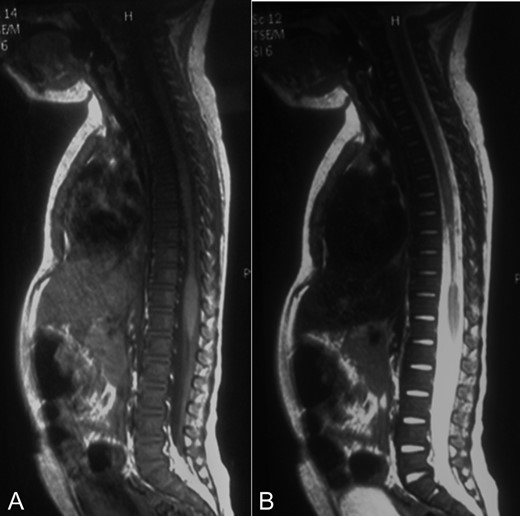

A 2-year-old female patient was referred to our institution after suffering a motor-vehicle accident. She was admitted under sedation with miotic pupils, left iliac hematoma and cervical collar. At admission, brain, chest, abdominal and pelvic CT scans reported right pneumothorax and a hyperdense hepatic lesion. Spine CT scan showed no fracture or any other pathologic findings (Fig. 1A).

A-B: A. Sagittal bone window of spine showing normal alignment and no fracture. B. Sagittal T1 contrast enhanced sequence showing a narrowed spinal cord from T7 to T10 that could correspond to gliosis and edema.